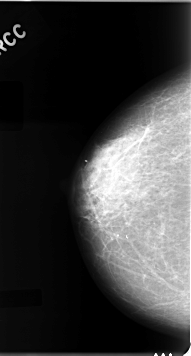

C_0050_1.RIGHT_MLO

RIGHT_CC LINES 4616 PIXELS_PER_LINE 2480 BITS_PER_PIXEL 12 RESOLUTION 50 NON_OVERLAY

RIGHT_MLO LINES 4664 PIXELS_PER_LINE 2584 BITS_PER_PIXEL 12 RESOLUTION 50 NON_OVERLAY